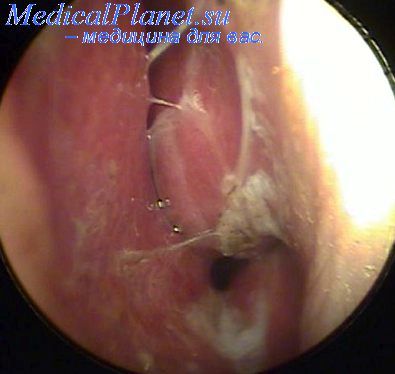

При передній риноскопії можна бачити сіру, бліду, ділянками як би налиту слизову оболонку переднього кінця або нижньої поверхні середніх носових раковин. Аналогічні зміни бувають на носовій перегородці в області tuberculum septi. Їх помилково іноді приймають за середню носову раковину.

При задній риноскопії можна бачити, що рожеві або бліді сірувато-жовті утворення, що нагадують по виду бульбашки, заповнюють хоани. При великих розмірах оточених задніх кінців середніх або нижніх носових раковин вони висуваються в носоглотку і можуть закривати задній край перегородки, частина іншої хоани, гирло євстахієвої труби. Якщо набряк захоплює окремі обмежені ділянки слизової оболонки заднього краю носової перегородки, остання випинається у вигляді кіст, наповнених серозно-слизової рідиною. З плином часу може відбуватися розсмоктування набряку рідини і розростання сполучної тканини з подальшим перетворенням набряку форми гіпертрофії в полипозную.

Характерною ознакою полипозной гіпертрофії є блідий, як би налитої вид кінців носових раковин, бульбашковидна, кістозна і гроноподібна форма їх і відсутність скорочення після змазування анемізуючі речовинами. Слід розрізняти полипозную форму гипертрофического нежиті від поліпів носа як самостійного морфологічного поняття. Незалежно від того, чи є поліп результатом набряку, продуктом запалення, продуктом зміненої реактивності організму або, нарешті, новоутворенням, один він або їх багато, поліп завжди представляє самостійне утворення, найчастіше поєднане з материнською тканиною за допомогою ніжки.

ознакою, відрізняє полипозную гіпертрофію. прийнято вважати широку основу перероджень слизової оболонки. Встановити це легко шляхом обмацування пуговчатий зондом. Вигідно буває при цьому застосувати попередню анемизацию носових раковин з метою розширення доступу до перероджень тканини. Часто з плином часу на грунті полипозной гіпертрофії розвиваються справжні поліпи.